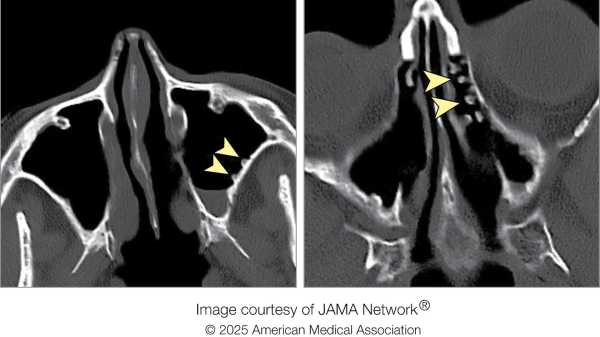

Комп’ютерна томографія голови пацієнтки показала, що її праві пазухи носа були настільки запалені, що виглядали непрозорими на знімку. При детальнішому розгляді було виявлено набряклі тканини, які зміщували жирові шари навколо ока. Також було виявлено скупчення гною в очниці, відоме як субперіостальний абсцес, написали лікарі у звіті про цей випадок.

Діагноз: Офтальмологи визначили, що набряк ока дівчинки був спричинений бактеріальною інфекцією, відомою як орбітальний целюліт, яка вражає жирову та м’язову тканини навколо ока, але не саме око. Це може призвести до постійної втрати зору, пошкоджуючи кровоносні судини та нерви в оці. Якщо інфекцію не лікувати, вона може поширитися в кровотік або мозок, що призведе до небезпечних для життя ускладнень. Лікарі визначили, що бактерії мігрували з початкової інфекції в зубах пацієнтки до пазух, а потім поширилися на око.

Лікування: Оскільки орбітальний целюліт може спричинити сліпоту та інші небезпечні ускладнення, лікарі хірургічно видалили абсцес, щоб зменшити тиск на око пацієнтки. Через кілька днів хірурги прооперували ще раз і видалили два інфіковані зуби: перший і другий моляри з правого боку. Вони створили дренажний отвір у пазухах пацієнтки та видалили кілька поліпів, що утворилися в порожнині пазухи. Вона продовжувала отримувати внутрішньовенні антибіотики, і її стан швидко покращився. Під час контрольного огляду через вісім місяців її око виглядало нормальним, без втрати зору чи рухливості.